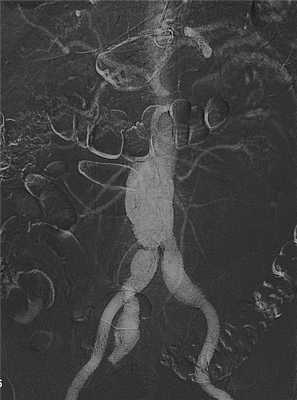

Аортография. Более травматичным, но у ряда больных совершенно необходимым, методом исследования является аортография (рис. 17.1). Она показана в клинически неясных случаях с целью установления окончательного диагноза. Но даже при установленном диагнозе разрыва АБА рентгеноконтрастное исследование дает ценную дополнительную информацию: 1) определение взаимоотношений аневризмы с висцеральными ветвями брюшной аорты, ее распространения на бифуркацию аорты и подвздошные артерии; 2) уточнение характера окклюзионных поражений висцеральных артерий и магистральных артерий конечностей; 3) выявление аортокавального свища. Следует отметить, что при аортографии не всегда удается подтвердить факт разрыва аневризмы, так как экстравазации контрастного вещества может не быть в связи с тампонадой дефекта стенки аневризматического мешка кровяными сгустками. Противопоказанием к аортографии является крайняя тяжесть состояния больного и нестабильная гемодинамика со снижением артериального давления ниже 90 мм рт.ст.